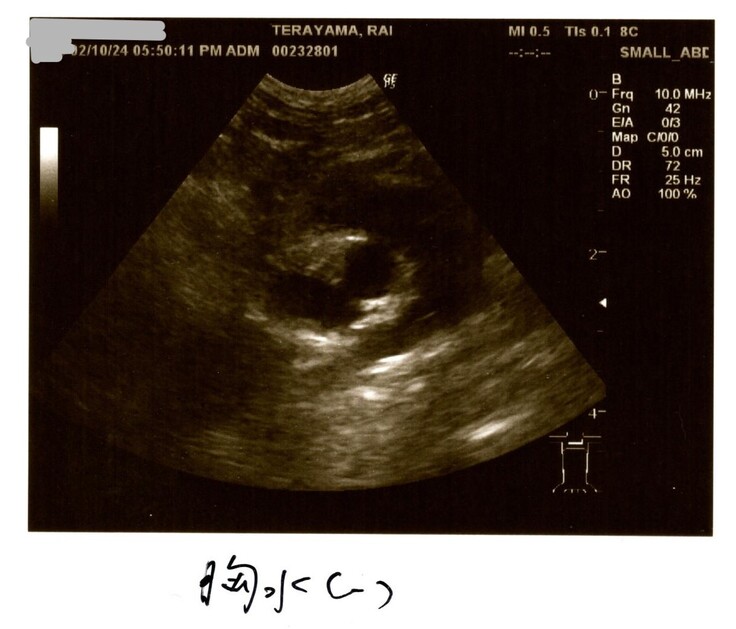

2/10検査結果

2/10はらいくんの2度目の検査結果を聞きました。

何と検査結果は全て改善していました!